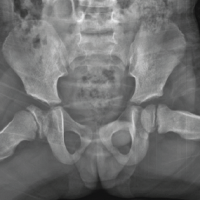

A 78-year-old male with previous medical history of rheumatoid arthritis, Type 2 diabetes mellitus, and AS presented for left THA due to non-union of ORIF of left acetabular fracture secondary to fall off of a ladder and post-traumatic arthritis. The patient had a pelvic X-ray significant for acute comminuted fracture of the left acetabulum with post-traumatic protrusion deformity that resulted in subsequent ORIF of left acetabulum over a year before the THA; pre-operative CT abdomen and pelvis and post-operative X-ray abdomen was not significant for vertebral fracture at this time (Fig. 1).

Figure 1: (Top left) pre-operative coronal computed tomography (CT) abdomen and pelvis significant for left acetabulum fracture and negative for lumbar fracture. (Top right) pre-operative sagittal CT abdomen and pelvis negative for lumbar fracture. (Bottom left) anterior-posterior (AP) X-ray film significant for left acetabulum fracture before open reduction and internal fixation (ORIF). (Bottom right) AP X-ray 1 week s/p ORIF of left acetabulum fracture, significant for lumbar vertebral degenerative changes and negative for lumbar fracture.

In the interval he had residual pain, limb-length discrepancy, weakness of left lower extremity, hip flexion contracture, low back pain, and foot drop. Neurosensory examination and films taken in the interval and in the pre-operative period were consistent with initial findings and significant for non-union of the left acetabular fracture. 14 months s/p ORIF X-ray was significant for non-union of acetabular fracture (Fig. 2), no imaging was taken in the interval to assess for lumbar pathology.

Figure 2: Anterior-posterior X-ray film significant for left acetabular non-union 14 months s/p open reduction and internal fixation.